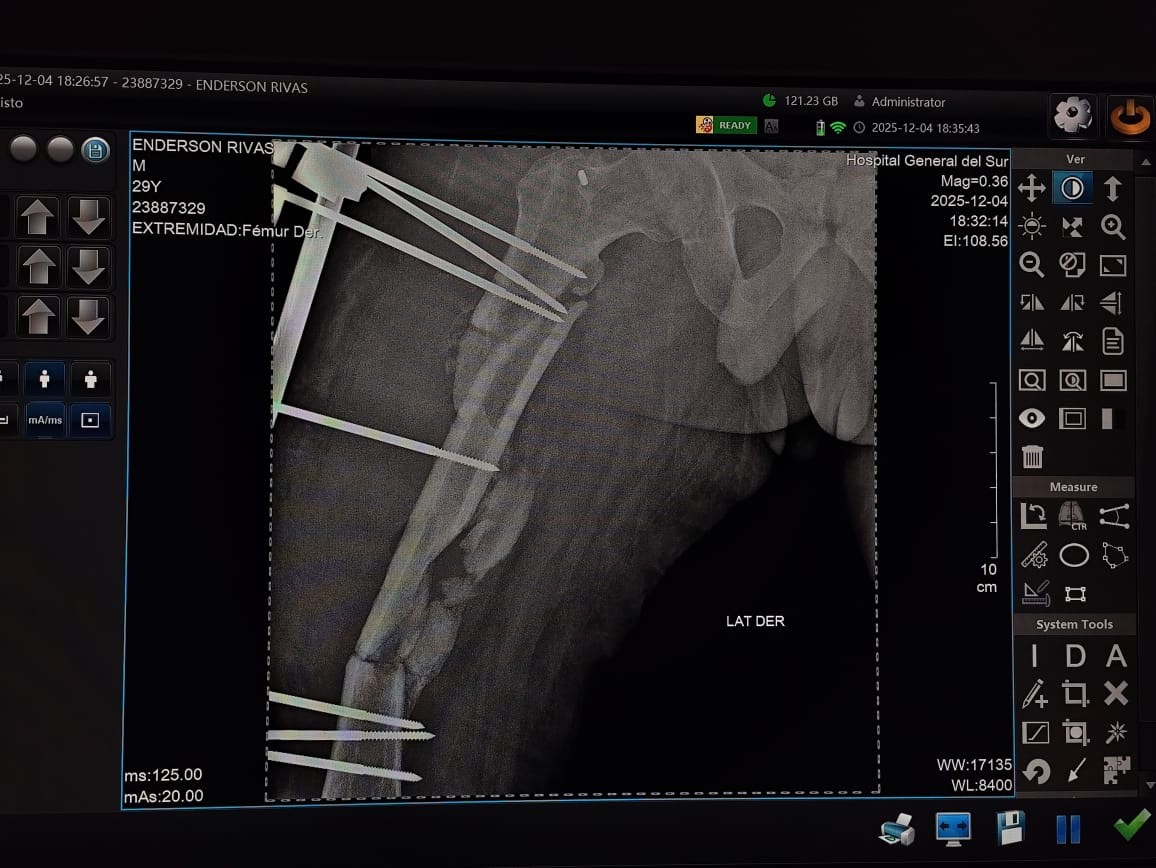

El pasado 23 de Febrero de 2025 , la vida de Enderxon Enrique Rivas Quintero cambió en un segundo. Mientras se desplazaba en su motocicleta, fue víctima de un accidente de tránsito de alta energía que le ocasionó lesiones graves en su pierna derecha. Enderxon es un joven de 30 años con toda una vida por delante, pero hoy se encuentra inmovilizado y a la espera de una cirugía urgente para no perder la funcionabilidad de su extremidad. El costo de los materiales de síntesis (clavos y pernos), los insumos médicos y los gastos postoperatorios superan nuestras posibilidades económicas actuales. Por eso, acudimos a tu buen corazón. Cada granito de arena cuenta para que Enderxon pueda entrar a quirófano lo antes posible y comenzar su rehabilitación."